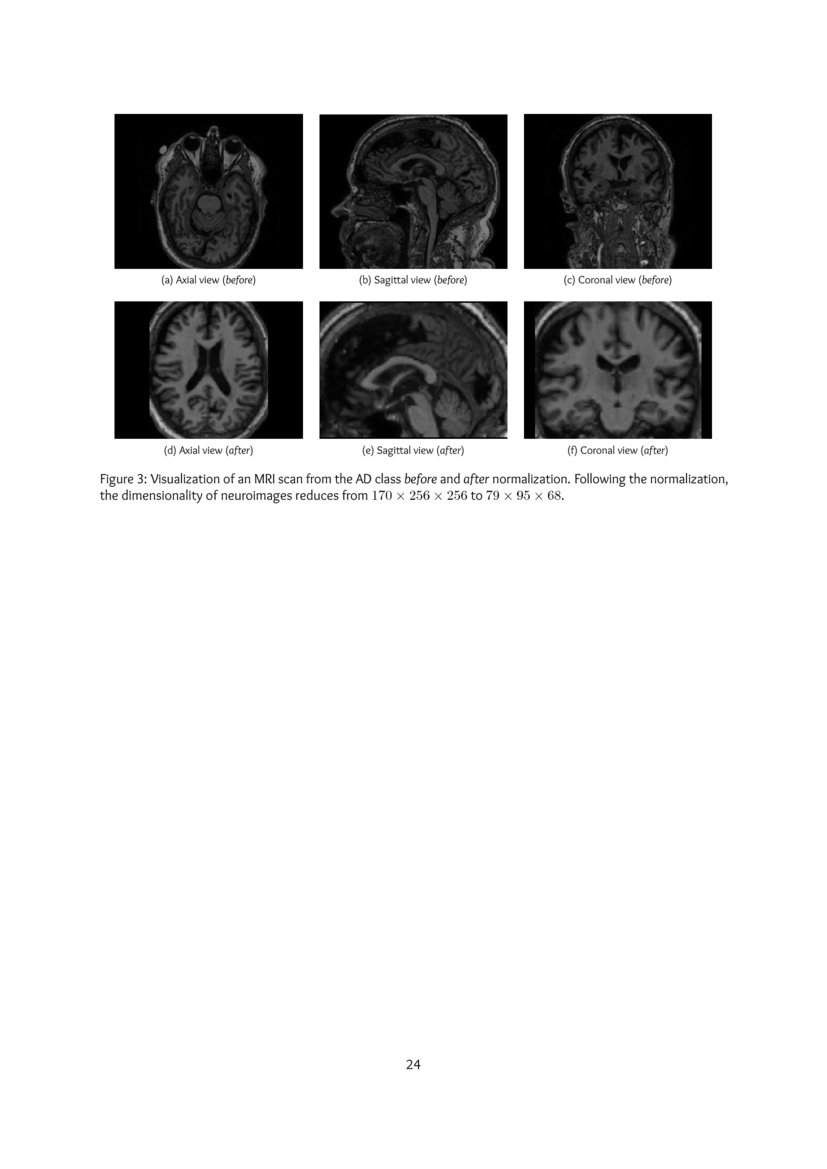

Volumetric Histogram Based Alzheimer S Disease Detection Using Support Vector Machine Ios Press

content.iospress.com